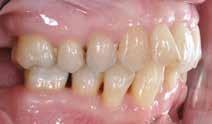

Behandlingen afsluttes med yderligere refinement-alignere for finindstilling af okklusionen, og efter 11 måneders ortodontisk behandling er der opnået normale relationer i alle tre

RESULTATER – Begge patienter opnåede sunde parodontale forhold, funktionel okklusion og forbedret æstetik. Ortodontisk behandling blev iværksat efter opnåelse af parodontal stabilitet og tilpasset det reducerede parodontium med kontrollerede kraftsystemer. Under behandlingen blev parodontiet vedligeholdt, og efter afsluttet ortodontisk behandling blev patienterne fulgt med regelmæssige kontroller af både parodontal sundhed og ortodontisk retention.

KONKLUSION – Ortodontisk behandling af patienter med velbehandlet parodontitis er mulig og kan give gode æstetiske og funktionelle langsigtede resultater med en interdisciplinær tilgang og efterfølgende fokus på vedligeholdelse og retention.